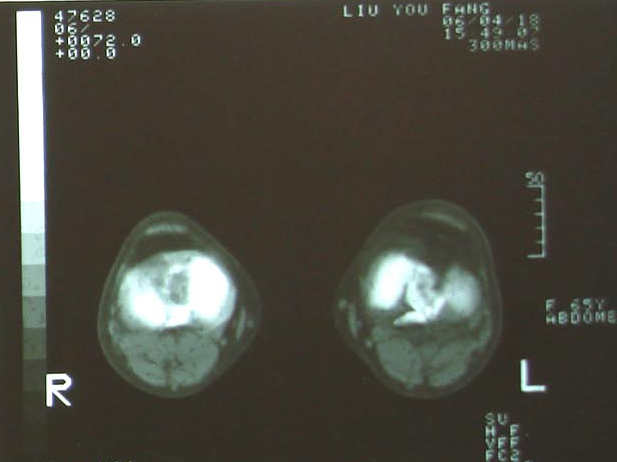

现在把ct结果公布,请大家继续讨论。

左胫骨髁间隆突骨折,建议ct检查!!

____关节囊内积血!!!

ct

平台骨折